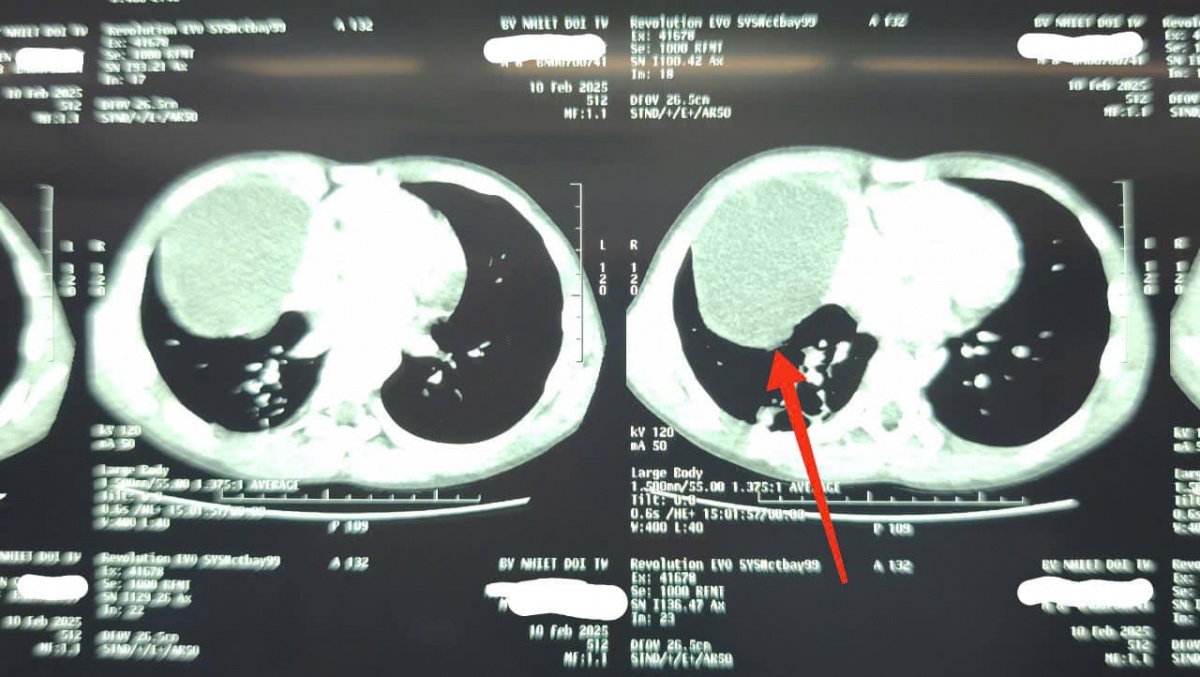

Hình ảnh chụp XQ của bé trai 8 tuổi. (Ảnh: BV Bệnh Nhiệt đới Trung ương)

Tại đây, các bác sĩ đã tiến hành các xét nghiệm và hình ảnh X-quang cho thấy có sự xuất hiện của dịch màng phổi và nang dịch. Sau khi chụp cắt lớp vi tính, kết quả cho thấy cháu B bị xẹp phổi, kèm theo khối u nang dịch trung thất, một bệnh lý bẩm sinh hiếm gặp.